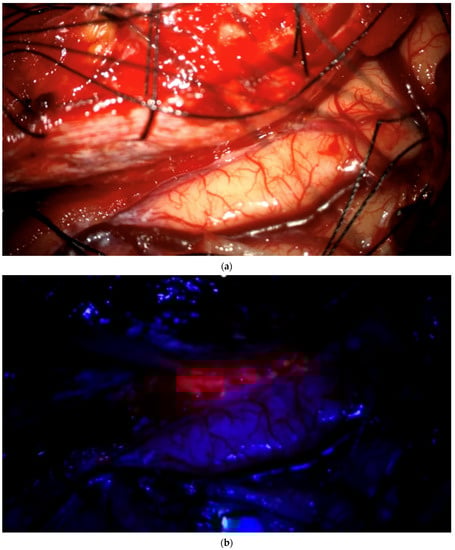

The aim of fluorescence assessment and tissue biopsy in bulk tumor is to determine whether a tumor shows fluorescence and to correlate fluorescence with tumor histology. To collect this biopsy, surgeons are asked to switch to blue light as soon as bulk tumor is encountered during surgery, to determine whether any fluorescence is visible and to take a biopsy from a fluorescing part of the tumor. A neuronavigation screenshot is taken from the exact location of the biopsy (Figure 1). The entire sequence is recorded using the microscope’s video system.

Biopsy acquisition from bulk tumor. As soon as surgeons encounter bulk tumor during surgery, they change to blue light, determine whether any fluorescence is visible, and, if so, take a biopsy from fluorescing tissue after taking a neuronavigation screenshot. The biopsy procedure is recorded for later assessment by the review panel. (a) Brain with visible bulk meningioma under elevated dura in a patient with tumor in the superior sagittal sinus infiltrating the adjacent brain. Insert shows pointer tip location marking the intended biopsy location. (b) Strong fluorescence of tumor under blue light, which is biopsied. (c) Neuronavigation screenshot (“F”: footwards; “H”: headward; “A”: anterior; “P”: posterior; “L”: left).